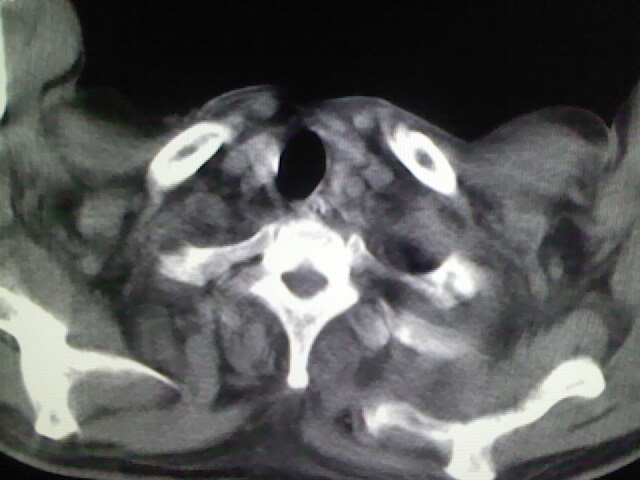

男,70岁,脑出血,长期卧床,左侧背部可触及肿块

食道里是什么

你放上去的